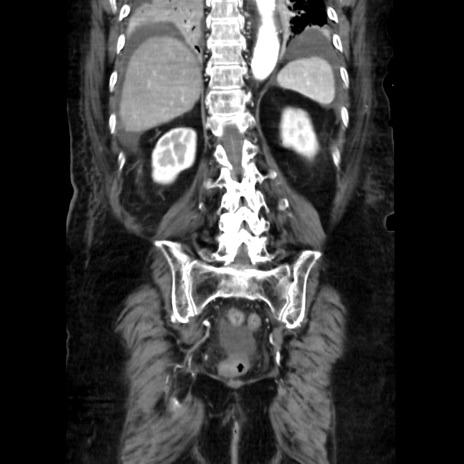

症例40(冠状断像)

【症例】90歳代女性

【主訴】腹痛・嘔吐

【現病歴】 食欲低下、嘔吐があり昨日他院受診。肺炎と診断され入院となる。入院後より腹部全体に圧痛あり。胃管留置され経過みていたが、症状持続するため、

当院転院となる。

【既往歴】胸椎圧迫骨折、胆石症

【身体所見】腹部:中央に激痛あり、圧痛あり、反跳痛不明

【データ】WBC 17100、CRP 18.82

冠状断像